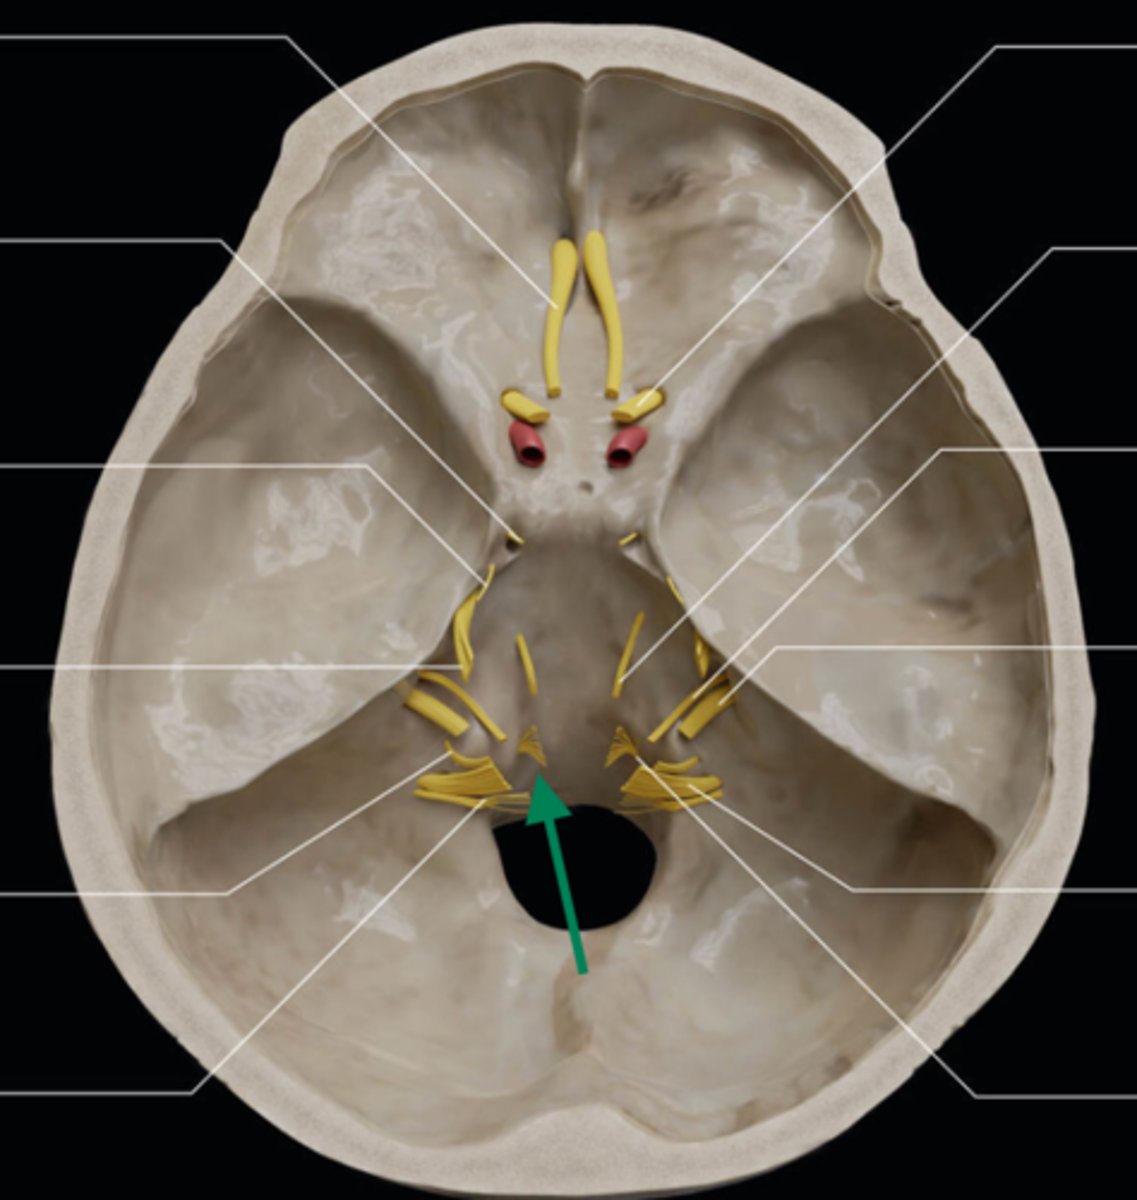

olfactory bulb

olfactory tract

optic nerve (CN II)

internal carotid artery

oculomotor nerve (CN III)

trochlear nerve (CN IV)

abducent nerve (CN VI)

trigeminal nerve (CN V)

facial nerve (CN VII)

vestibulocochlear nerve (CN VIII)

glossopharyngeal nerve (CN IX)

vagus nerve (CN X)

accessory nerve (CN XI)

hypoglossal nerve (CN XII)

optic chiasm

trigeminal ganglion

anterior cranial fossa